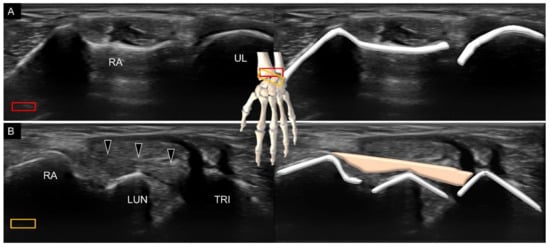

3.1. Attachment to the Capitate

Attachment to the Triquetrum

6. Sonoanatomy of Dorsal Intrinsic Carpal Ligaments